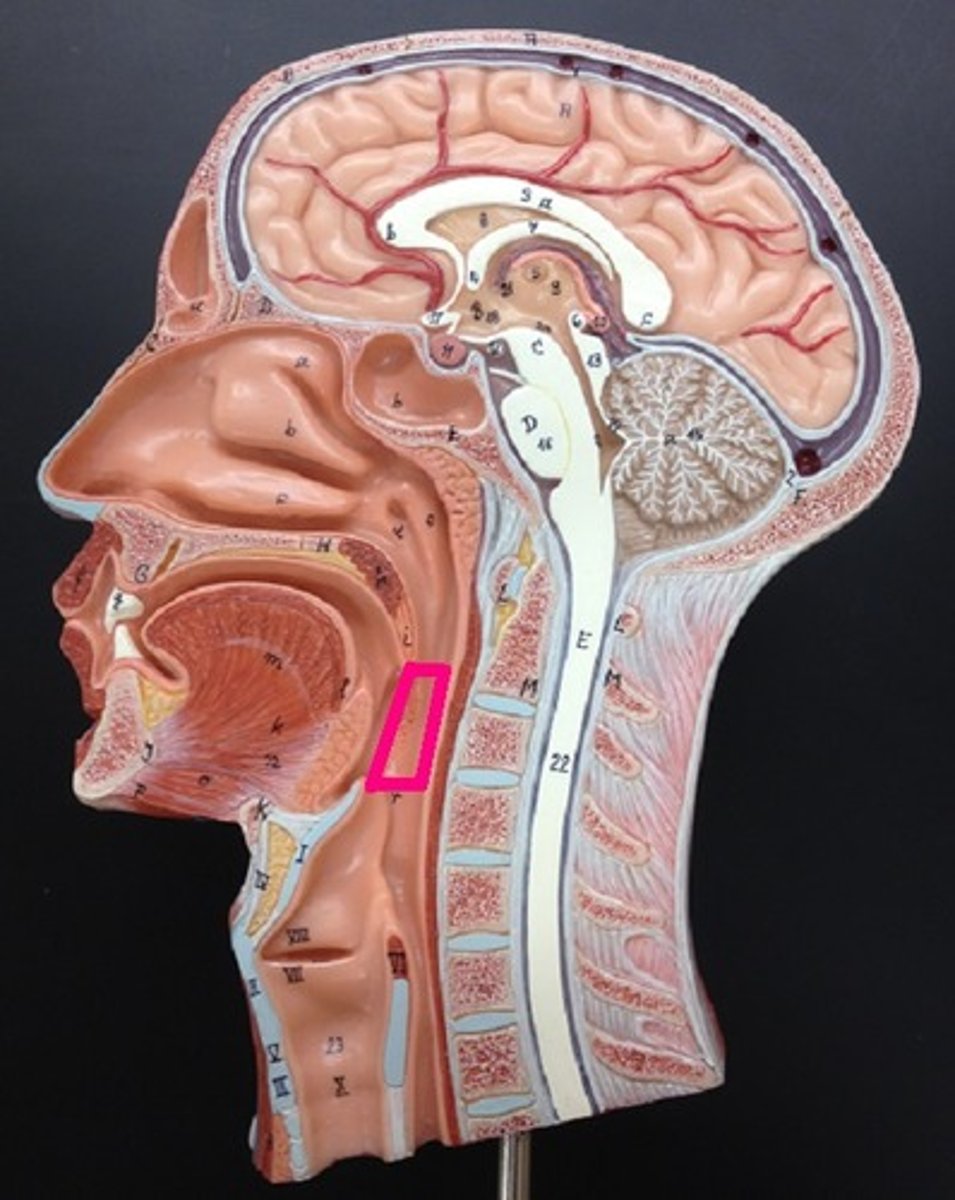

Pharynx

oropharynx

Epiglottis

laryngopharynx